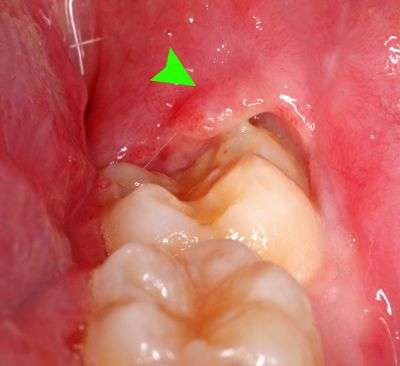

Viêm nướu trùm xảy ra khi phần nướu che phủ lên răng (thường là răng khôn), tạo thành một “khe hở” giữa nướu và răng.

Khe này rất dễ tích tụ:

- thức ăn

- vi khuẩn

- mảng bám

Lâu ngày sẽ gây viêm nhiễm, sưng đau và khó vệ sinh răng miệng.

- nướu sưng đỏ quanh răng khôn